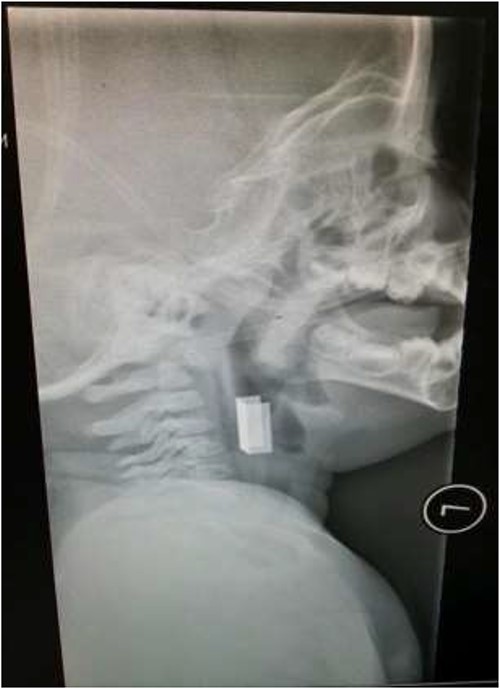

The second case involved a 3-year-old child who presented with sudden onset noisy breathing. Inspiratory stridor was evident on examination. Radiographs of the neck again showed a radio-opaque object in the upper airway (Fig. 4). Apnoeic oxygenation allowed for tubeless anaesthetic and safe removal of the metallic foreign body from the airway (Fig. 5).

Lateral neck X-ray showing a radio-opaque object in the upper airway.